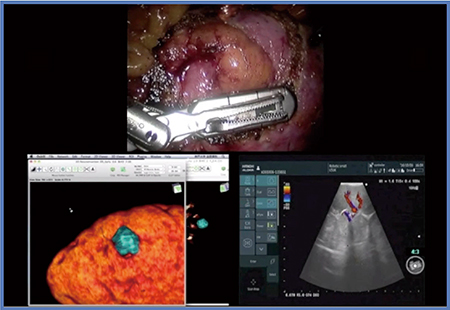

症例3は,63歳,男性,左腎細胞がんで,RNSは7pである(図4)。完全埋没型の腫瘍であり,後腹膜アプローチにてRAPNを施行した。マーキングの方法は基本的には症例2とほぼ同じであるが,完全埋没型の腫瘍の場合はCTの3D画像があっても,術中エコーでマージンをしっかり確認しないと手術は困難である。本症例は切除断端陰性で,出血は少量,阻血時間は19分であった。

図4 症例3:RNS 7pの左腎細胞がん(63歳,男性)